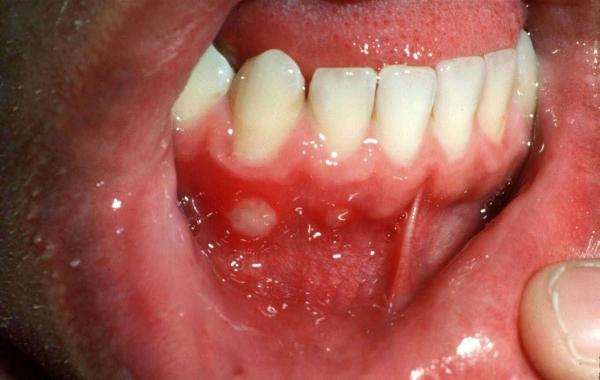

Фото 4. Запалені ділянки розташовується на небі і горлі, мають малиновий колір з білими вкрапленнями.

На ерозіях з’являється наліт білого або жовтого кольору. Під плівкою на уражених тканинах утворюються виразки. Гострий тонзиліт протікає важко, особливо у дитини. У хворого піднімається температура тіла, проковтування їжі і напоїв викликає хворобливі відчуття, з’являється підвищене слиновиділення.

Дорослі легше переносять захворювання. Температура невисока, спостерігається почервоніння горла, набряк слизових оболонок. На поверхні можна побачити болючі виразки. Іноді при захворюванні збільшуються лімфатичні вузли.